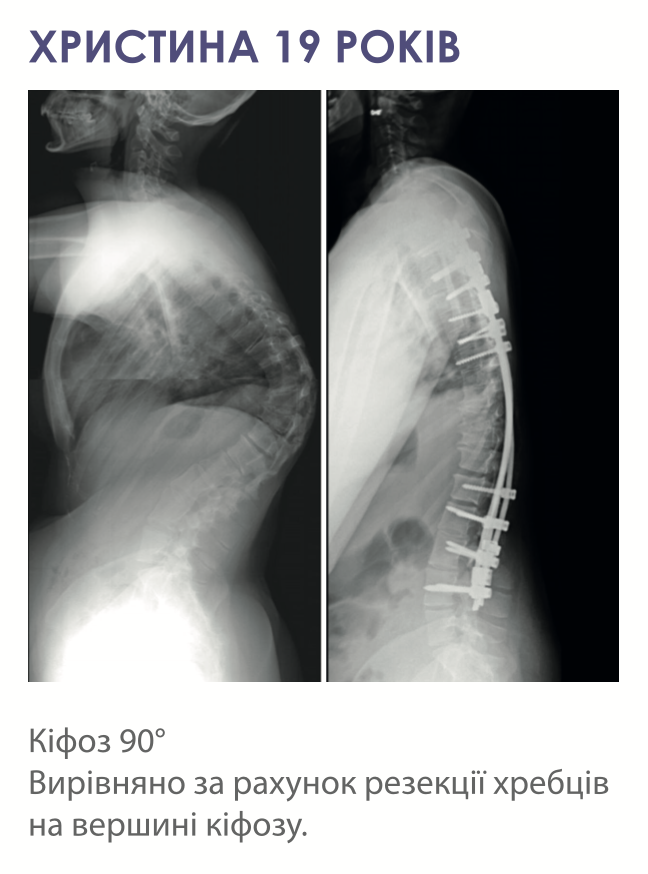

- З частковим або повним видаленням деформованих хребців – проводиться при виражених та екстремальних(кут викривлення більше 90°) викривленнях, при не гнучких та зрощених сколіозах та у випадку аномалій розвитку хребта.